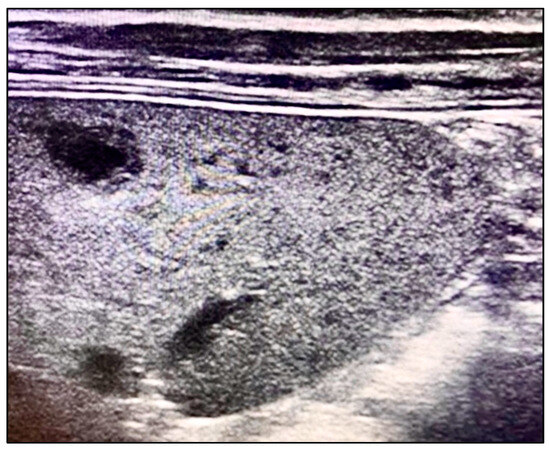

We aimed to systematically review the laboratory and ultrasound imaging data from pediatric patient registries to identify key diagnostic variables related to systemic B. henselae infection. Our analysis focused on detecting morphological changes in the spleen using ultrasound imaging. We specifically looked for the presence of multiple hypoechoic lesions with clearly defined thick margins, a characteristic finding illustrated in Figure 1. Bone marrow aspiration was included as part of our diagnostic protocol to rule out differential diagnoses such as lymphoma.

Figure 1. Multiple hypoechoic lesions with well-defined thick margins on ultrasound.